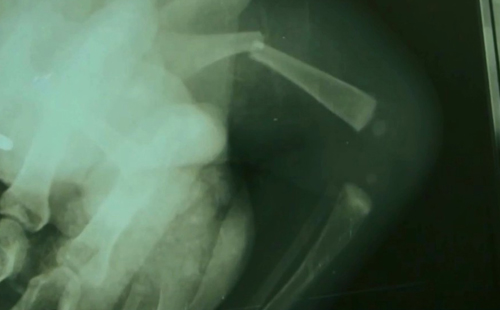

Um raio x feito em um bebê de três meses que morreu na terça-feira (27), em Vitória da Conquista, sudoeste da Bahia, após levar tapa no rosto dado pela própria mãe, mostra uma fratura no fêmur que ele sofreu duas semanas antes de morrer.

Na imagem do exame, é possível ver o osso do recém nascido partido. Após a morte do bebê, a mãe, Graciane Almeida Silva, foi presa em flagrante.